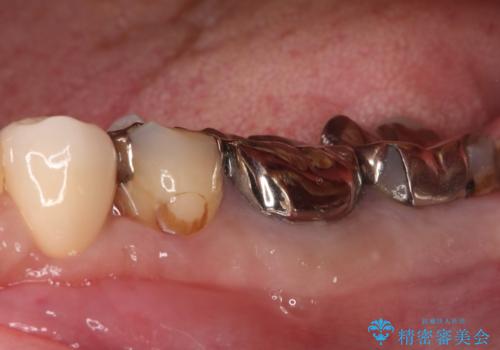

- 左下4番の奥歯に、歯肉の下まで進行した深い虫歯を認め来院されました。通常であれば神経を抜く必要があるほど深い虫歯でしたが、患者様の歯をできる限り保存するため、歯の神経を抜かずに残すことを目指す治療計画を立案。歯肉の下にある虫歯を適切に治療するため、歯周外科処置で歯肉のラインを調整した上で、精密なセラミッククラウンで修復することになりました。

まず、虫歯を徹底的に除去するために、歯周外科処置で歯肉のラインを調整し、治療部位を露出させました。その後、神経に近接した深い虫歯を慎重に除去。神経の保護処置を施し、歯の神経を抜くことなく保存することができました。型取りから、患者様の歯の色や形に合わせたオーダーメイドのセラミッククラウンを作製。最終的に、精度の高いクラウンを装着し、咬み合わせを細かく調整しました。これにより、神経を温存しながら、虫歯の再発を防ぎ、快適な咬み心地を取り戻していただけました。